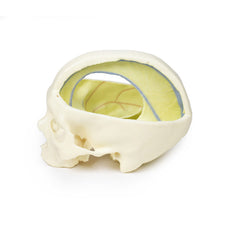

Cranial Cavity: The left and right orbits have been opened to reveal the orbital nerves and vessels along with the eyes and optic nerves. The optic chiasm, optic tracts and the lateral geniculate bodies are retained thus showing a large part of the visual pathways. The brainstem is cut at the level of the superior colliculi on the left and slightly lower on the right. The olfactory tracts and bulbs are also demonstrated. The origins of many of the cranial nerves from the brainstem are clearly visible.

Cranial Cavity: The left and right orbits have been opened to reveal the orbital nerves and vessels along with the eyes and optic nerves. The optic chiasm, optic tracts and the lateral geniculate bodies are retained thus showing a large part of the visual pathways. The brainstem is cut at the level of the superior colliculi on the left and slightly lower on the right. The olfactory tracts and bulbs are also demonstrated. The origins of many of the cranial nerves from the brainstem are clearly visible.